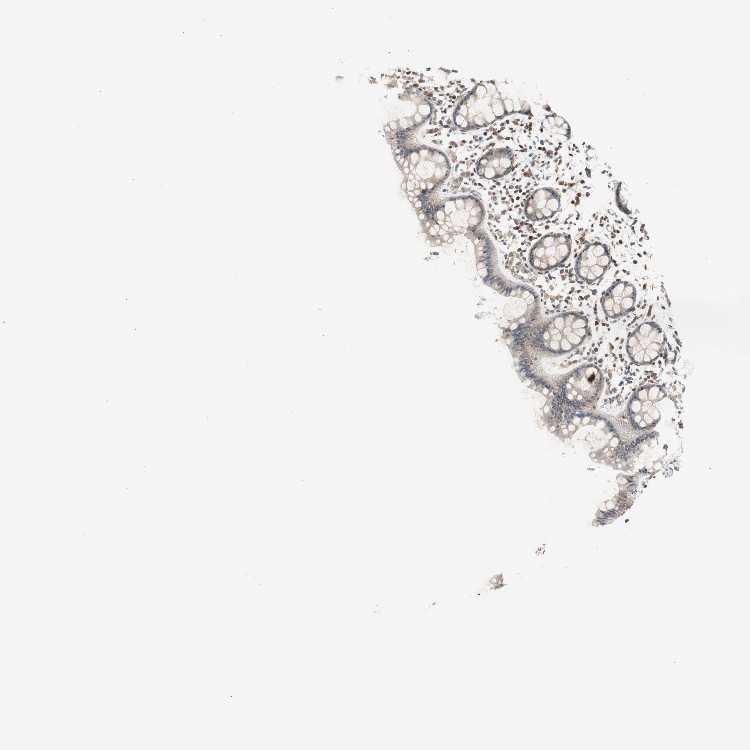

POLH